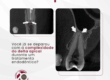

Perfurações radiculares podem passar despercebidas na radiografia, se sobrepõe à raiz — como neste caso.

É por isso que, na IRDO, indicamos a CBCT sempre que o exame 2D não oferece base suficiente para condução.

Não se trata apenas de ver mais, mas de interpretar com clareza o que antes era apenas hipótese.

Quando o 2D não esclarece

- Radiografia periapical sem achados evidentes.

- Paciente sintomático.

- Hipóteses clínicas, mas sem confirmação.

Desse modo, em quadros assim, a diferença está na escolha do exame certo.

A CBCT revelou:

– Perfuração vestibular na zona de risco

– Comunicação com o periodonto

– Área de reabsorção óssea associada

Ou seja: a imagem mudou o entendimento do caso — e a conduta.

A tomografia permite:

– Identificar o trajeto da perfuração

– Avaliar a relação com estruturas periodontais

– Medir extensão, direção e profundidade da lesão

“A CBCT deve ser considerada sempre que a imagem 2D não for conclusiva, especialmente em casos de suspeita de perfuração radicular.”

AAE – Position Statement – 2020

Dessa forma, indicação respaldada, decisão clínica com mais segurança.